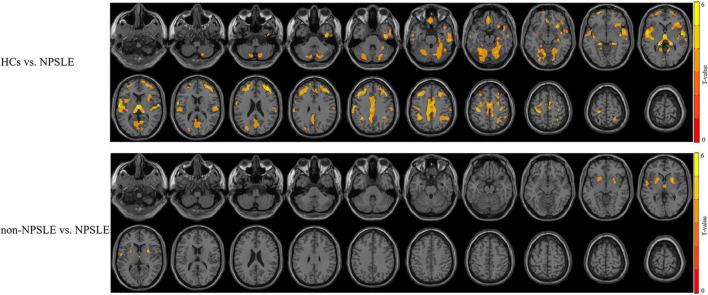

54 female patients with SLE (30 NPSLE and 24 non-NPSLE) and 32 matched healthy controls were recruited. All subjects received a quantitative MRI scan (FLAIR, 3DT1, resting-state functional MRI). GM volume (GMV), fractional amplitude of low-frequency fluctuation (fALFF), regional homogeneity (ReHo), and degree of centrality (DC) were obtained. Between-group comparison, clinical correlation, and discrimination of NPSLE from non-NPSLE were achieved by voxel-based analysis, cerebellar seed-based functional connectivity analysis, regression analysis, and support vector machine (SVM), respectively.

Patients with NPSLE showed overt subcortical GM atrophy without significantly abnormal brain functions in the same region compared with controls. The dysfunction within the left superior temporal gyri (L-STG) was found precede the GM volumetric loss. The function of the nodes in default mode network (DMN) and salience network (SN) were weakened in NPSLE patients compared to controls. The function of the cerebellar posterior lobes was significantly activated in non-NPSLE patients but attenuated along with GM atrophy and presented higher connectivity with L-STG and DMN in NPSLE patients, while the variation of the functional activities in the sensorimotor network (SMN) was the opposite. These structural and functional alterations were mainly correlated with disease burden and anti-phospholipid antibodies (aPLs) (r ranges from -1.53 to 1.29). The ReHos in the bilateral cerebellar posterior lobes showed high discriminative power in identifying patients with NPSLE with accuracy of 87%.

与对照组相比,NPSLE患者表现出明显的皮质下脑灰质萎缩,且同一区域的脑功能无明显异常。发现左侧颞上回(L-STG)的功能障碍先于脑灰质体积减少。与对照组相比,NPSLE患者默认模式网络(DMN)和突显网络(SN)中的节点功能减弱。非NPSLE患者小脑后叶功能显著激活,但随着脑灰质萎缩而减弱,在NPSLE患者中与L-STG和DMN的连接性更高,而感觉运动网络(SMN)中功能活动的变化则相反。这些结构和功能改变主要与疾病负担和抗磷脂抗体(aPLs)相关(r范围为-1.53至1.29)。双侧小脑后叶的ReHo在识别NPSLE患者方面具有较高的鉴别力,准确率为87%。